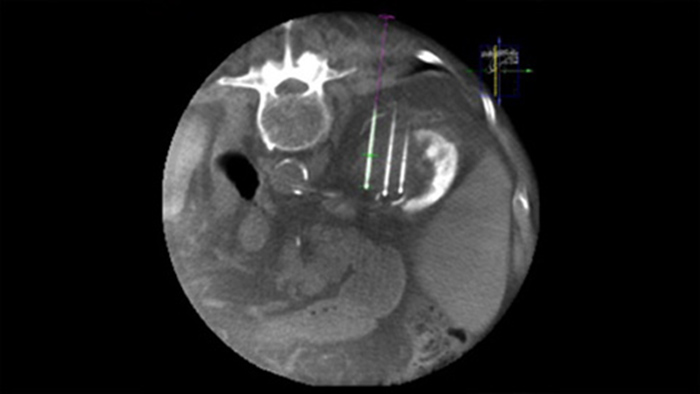

SmartCT Soft Tissue offers a Cone Beam CT (CBCT) acquisition technique augmented with step-by-step guidance, advanced 3D visualisation and measurement tools; all accessible on the touch screen module at table side.

Dual View allows the overlay of a pre-procedure 3D image (CT/MR/PET-CT) on an intra-procedure 3D CBCT Dual to better visualisation the lesions and access critical input for needle planning.

XperGuide provides highly accurate live image guidance of each needle to a targeted position by overlaying pre-planned trajectories with fluoroscopic imaging.3